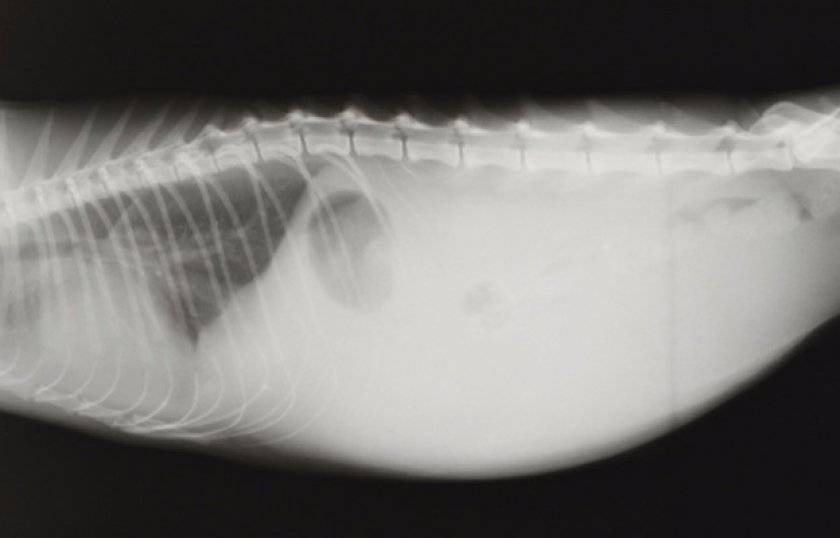

Выпотной (влажный) ФИП — наиболее тяжёлая клиническая форма, которая быстро приводит к летальному исходу. Она характеризуется выпотом в брюшную полость. Наряду с этим в 20% случаев присутствуют выпоты в плевральную полость и перикард, главным клиническим симптомом в таких случаях является затруднённое дыхание. Наблюдаются исхудание, анемия, лихорадка, рвота, диарея, возможно развитие перикардита, печеночной недостаточности. Может наблюдаться желтуха, особенно на поздних стадиях болезни. Поражение глаз и центральной нервной системы наблюдается в 10% случаев заболевания выпотным перитонитом. Смерть наступает в течение 1-2 месяцев.

- Рентгенографию (для определения наличия асцита брюшной полости).

Экссудативный («мокрый») сценарий связан с выработкой и выходом значительного объема жидкости, поступающей в брюшную или грудную полость. Заметить этот процесс просто:

- также может увеличиться живот; в тяжелых случаях туда может попасть до 1 литра экссудата;

- вздутие живота из-за скопления жидкости в брюшине.